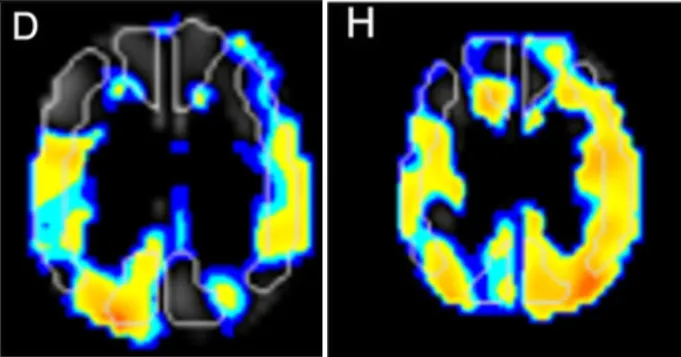

所幸手术取得圆满成功。术后复查显示新建“枕动脉-大脑中动脉”通路通畅,小智的头痛、视力模糊及肢体无力症状完全消失;单光子发射计算机断层扫描(SPECT)显示其大脑中动脉及大脑后动脉供血区的“脑血管反应性”(CVR)显著提升——表明大脑应对血流变化能力增强,未来缺血风险大幅降低。

术前SPECT成像显示左大脑中动脉及大脑后动脉区脑血管反应性降低(图D)。

术后SPECT成像显示大脑中动脉及大脑后动脉区脑血管反应性显著改善(图H)。